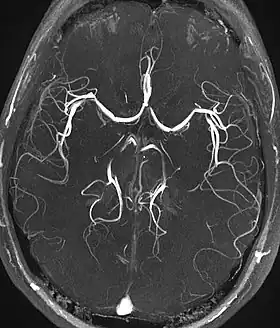

| Magnetic resonance angiography (MRA) and venography | Time-of-flight | TOF | Blood entering the imaged area is not yet magnetically saturated, giving it a much higher signal when using short echo time and flow compensation. | Detection of aneurysm, stenosis, or dissection[40] | ![]() |